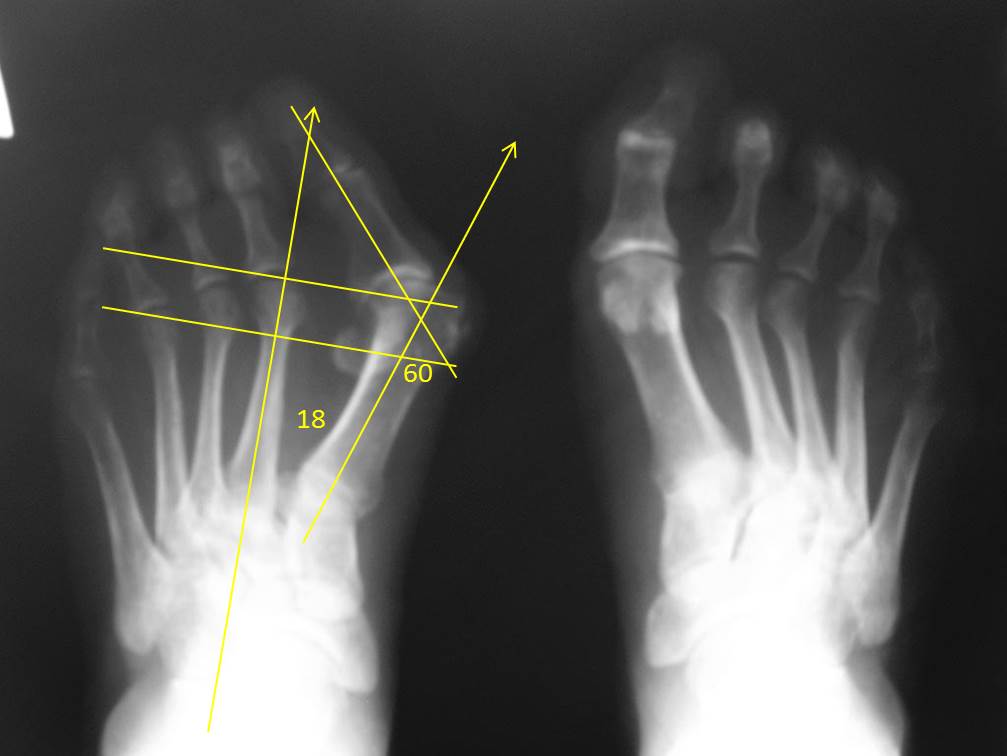

Насчет "Как по-моему должен звучать диагноз" - явная переоценка возможностей. По одному снимку ведь невозможно определить, есть ли молоткообразная деформация средних пальцев? Отклонение кнаружи 2-3 пальцев является самостоятельной деформацией или это следствие давления на них первого пальца и при прекращении давления они самостоятельно становятся на место? Ясно одно - имеется выраженная (грубая) вальгусная деформация первого пальца. Обо всех остальных компонентах деформации судить по одной рентгенограмме невзможно. Если натоптышей под головками центральных плюсневых костей нет, можно их не трогать. Все-таки по снимку имеется значительное преобладание длины первой над длинами латеральных плюсневых костей. Я сделал разметку на рентгенограмме и это сразу стало хорошо видно: перпендикуляр к оси 2 плюсневой, проведенный через латеральную сесамовидную кость расположен дистальнее середины головки 4 плюсневой (в норме проходит через середину головки), а такой же перпендикуляр, проведенный через верхушку головки второй плюсневой проходит на 2 мм проксимальнее суставного края головки первой плюсневой. В норме - первая плюсневая равна или короче второй. Так что, наиболее вероятный план - остеотомия первой плюсневой и основной фаланги первого пальца. С укорочением первой плюсневой до 2-3 мм.

еще раз рассмотрел стопу, все же натоптыши есть и под головками плюсневых 2-5. Если делать остеотомию 2-4 по Вейль, то насколько придется укоротить 1 плюсенвую? Учитывая натоптыш снизу и сбоку в проекции 5 плюсневой трогать ли ее? Спасибо за рисунок и подробную раскладку.

по-видимому, предоперационный план вырисовывается такой- scarf с укорочением 1 плюсневой на 2-3мм, остеотомия основания основной фаланги первого пальца по Akin, остеотомия 2-4 плюсневых по Вейль. Остается вопрос по молоткообразной деформации, она в основном выражена во 2 пальце- стоит ли ее корригировать и каким способом. Еще хотелось бы уточнить какие винты Вы используете. Спасибо.

По своей концепции scarf - суставосохраняющая остеотомия, поэтому не вижу показаний к Брандесу(Келлеру). Не очень понял про аллотрансплантат - вы планируете делать стяжку? По идее Weil 2-3(4?) будет достаточно. Первый палец должен "выводиться" - межплюсневый угол не очень большой, однако потребуется значимое укорочение 1 луча (на вскидку около 8-10 мм - но посчитайте по Рг сами).